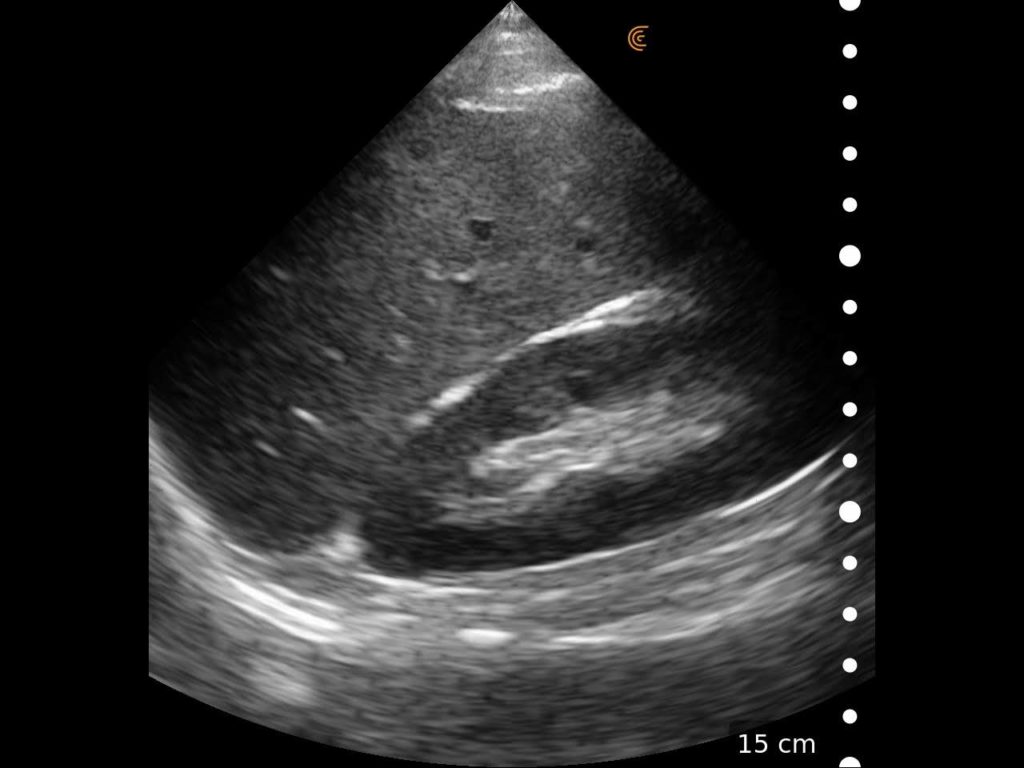

Desempenhe exames cardíacos à beira-leito com imagens de alta resolução em um transdutor sem fio.

Pequeno e com imagens profundas, o Clarius PA HD3 oferece imagens do tórax e abdômen de altíssima definição em até 40cm.

É a principal escolha para médicos que procuram imagens cardíacas diferenciadas em um transdutor ultraportátil perfeito para exames FAST, imagens superficiais e transcranianas.

Com 192 elementos e tecnologia de 8 feixes, o Clarius entrega alta performance nos ultra portáteis com qualidade de imagem e recursos equiparáveis aos equipamentos high end convencionais.